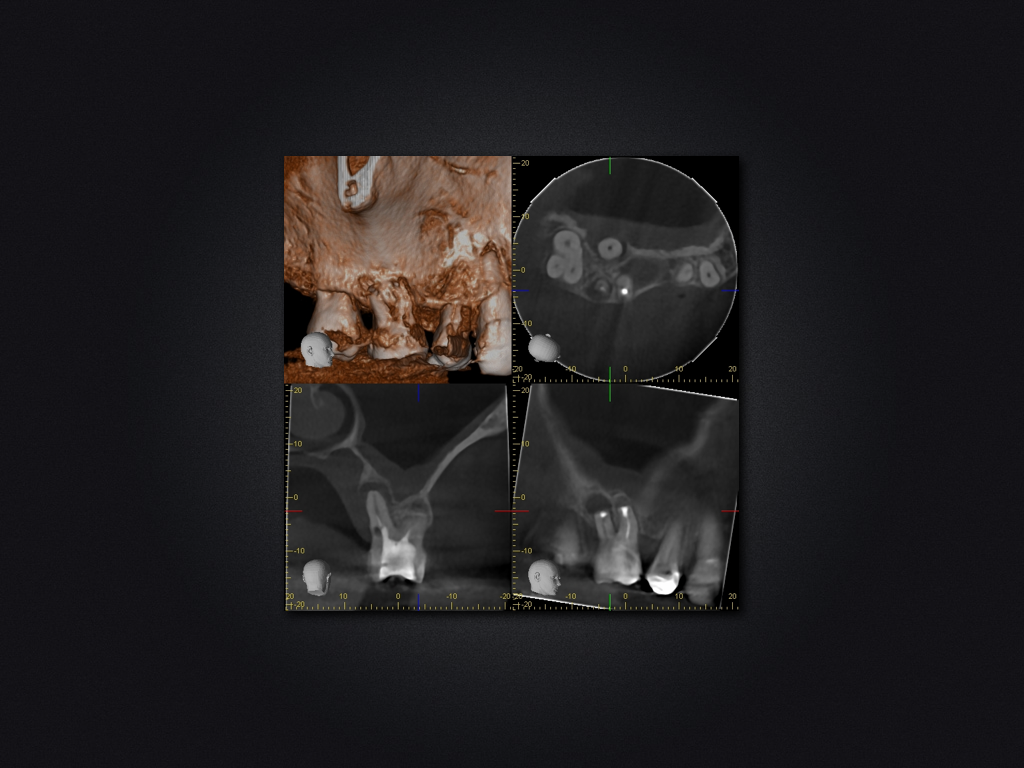

16D.003

Saving Hopeless Teeth (XXX)